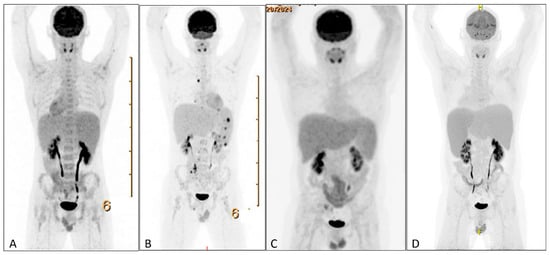

HLH can arise secondary to infections, autoimmune disorders, and malignancies, particularly lymphomas. Therefore, a broad diagnostic workup was initiated. Infectious screening revealed negative blood cultures, no malaria, and negative serologies for CMV; HIV; HSV-1/2; HHV-6/8; Tropheryma whipplei; Mycobacterium tuberculosis; hepatitis A, B, and C; Treponema pallidum; Toxoplasma gondii; and Leishmania spp. PCR testing revealed EBV DNA at 533,000 copies/mL, with positive EBNA IgG and VCA IgG and negative IgM. Urine tests were negative for M. tuberculosis, Histoplasma spp., Chlamydia trachomatis, and Neisseria gonorrhoeae. Hematologic evaluation showed no clonal B- or T-cell populations on flow cytometry or clonal T-cell receptor gene rearrangements on peripheral blood. Autoimmune serologies (ANA and anti-dsDNA) were negative. Also the bone marrow biopsy showed no morphological or immunophenotypic evidence of malignancy, infection, or clonal lymphocytes. Stains for microbial agents were negative, and the karyotype was normal. Scattered EBV-positive cells were present but too sparse for further characterization (Figure 2A–C). A PET scan revealed splenomegaly (18 cm, Figure 3A) without significant FDG uptake, increased bone marrow uptake, and no thymic abnormalities. The patient was admitted for further workup, and dexamethasone 20 mg daily was initiated.

Following dexamethasone, the patient improved, allowing discharge (Figure 1). A splenic biopsy showed active inflammation with EBV-encoded RNA (EBER) positivity but no evidence of B- or-T-cell lymphoma, including assessment of clonality. As this case involved an outpatient, ferritin and EBV load decreased, and dexamethasone was tapered. Whole-exome sequencing (WES) for primary immunodeficiency and HLH-related genes was negative. Six weeks later, fever recurred with new FDG-avid splenic nodules, bone lesions, and mesenteric lymphadenopathy on PET-CT (Figure 3B). Mesenteric biopsies were inconclusive; repeating the splenic biopsy showed no lymphoma but a reactive T-cell influx, though limited tissue precluded further analyses (Figure 4A–C). Skin biopsies showed no intravascular lymphoma. Re-treatment with dexamethasone and rituximab transiently reduced EBV load and ferritin. However, upon another rise in ferritin and EBV levels, HLH-94 therapy (dexamethasone, etoposide, and IVIG) was initiated, without lasting response. Ruxolitinib was added, achieving only temporary improvement, and the patient was transferred to the academic hospital (Figure 1).

After referral, PET-CT was repeated and showed resolution of prior lymphadenopathy and no splenic FDG uptake, though splenomegaly persisted (18 cm; Figure 3C). Cell sorting revealed high EBV loads in NK cells (500,000 copies/105 cells), T cells (90,000), and monocytes (200,000), supporting CAEBV. Additional analyses for AP/XIAP expression and NKG2D were negative. With the working hypothesis of CAEBV, CHOP-etoposide was initiated, and allogeneic stem cell transplantation was planned, but an EBV flare recurred within two weeks. At this point, peripheral blood sent for the immune deficiency panel was analyzed using a WES-based panel for the presence of DNA structural variants and DNA copy number abnormalities. Due to an aberrant pattern for the DNA copy number analysis, which could not be of constitutional origin, additional whole-genome SNP-array analysis was performed. In 20–50% of cells this resulted in (XY, +X[0.2], del(X)(q11q26)[0.2], dup(2)(q23q35)[0.3], +6[0.2], dup(6)(q12q16)[0.3], del(6)(q16)[0.2], del(6)(q16q25)[0.2], hmz(17)(pterp11)[0.5], +20[0.3], del(20)(p12)[0.3]). These copy number changes might be consistent with a malignancy of lymphoid origin. In light of these cytogenetic abnormalities, specifically, loss of heterozygosity of a large part of the short arm of chromosome 17, whole-exome sequencing data on peripheral blood was re-evaluated, showing a pathogenic variant in TP53 on 17p13 (NM_000546.6(TP53):c.817C>T, p.(Arg273Cys)), with a variant allele frequency of 31%.

During a subsequent HLH flare, PET-CT revealed progressive splenomegaly with increased FDG uptake (Figure 3D). A third splenic biopsy showed an atypical infiltrate of small and scattered larger cells with irregular nuclei. The cells were positive for CD2, CD3, CD56, granzyme B, TIA1, and EBER; CD56/EBER double staining confirmed the atypical population. CD30 was weakly positive (1–5%). p53 showed nuclear overexpression with high proliferative activity (75%). CD5, CD7, CD8, MUM1, TCRab, TCR-delta, TdT, and CD20 were negative. No clonal T-cell population was detected. The findings support EBV-positive extranodal NK/T-cell lymphoma (Figure 4C–F). The patient was treated with D-GDP (cisplatin, dexamethasone, gemcitabine, and peg-asparaginase) [5], resulting in clinical improvement and a reduction in EBV load and ferritin levels. Ruxolitinib and dexamethasone were tapered.

Figure 3. PET scans during clinical course. (A) PET-CT showing splenomegaly without increased FDG-uptake. (B) PET-CT showing additional mesenterial lymphadenopathy, FDG-avid splenic nodules, and bone lesions. (C) PET-CT showing normalization of FDG-avid lymphadenopathy and splenomegaly without increased FDG uptake. (D) PET-CT showing increased splenomegaly with increased FDG uptake. PET = positron emission tomography. FDG = 18fluorodeoxyglucose.